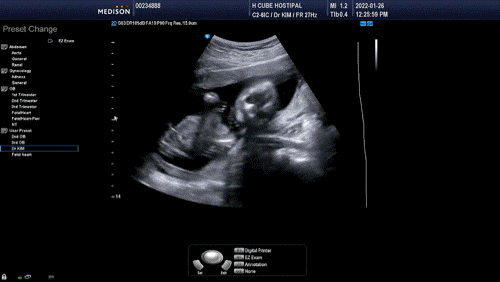

17주 2차 기형아 검사 2022.01.26

입덧약 받으러 갔을 때 본 지 3주 만의 오공 씨워낙 시끄러워 원장이 보기 힘들다고 말할 정도로 파워 무빙 중이었다.초코우유 덕분인지는 모르겠지만 실은 손발이 생긴 뒤 초코우유를 먹으려고 안 먹어도 볼 때마다 떠들지 않았던 적이 없는 것 같다?매우 활동적인 아들 같은 예다.

오늘 성별을 제대로 확인할 수 있을 거라 생각했는데 이번에도 역시 다리 사이의 완벽한 존재감?오공은 반전 없이 역시 아들이라는 결정을 내렸다.

실제로 14주 초음파로 완벽하게 확신한 나와 달리 남편은 일말의 반전을 기대하는 눈치여서 맘카페에서 같은 주수의 딸의 초음파까지 찾아 보였다.이 정도의 주수에 정말 강력한 다리 사이에 삼각점이 반전될 확률은 거의 없다고, 오공은 아들이니 그대로 받아들이라고 미리 학습시킨 덕분에 이미 병원에 가기 전부터 우리는 아들이야. 하고 있기에 다시 만난 오공의 다리 사이에 그놈을 보고도 역시! 하고 확인받는 기분이었다.

원장도 길게 말은 하지 않고 다리 사이로 봤죠?난 보여줘!!라고 말하며 마셨다. 아들의 성별 확인은 오래 말할 것도 없이 쉽고 빨리 끝나는구나.

약간 묵직하게 다리가 긴 붉은 도련님의 오공배를 볼 때마다 잘록하다는 생각처럼 복부 둘레는 조금 넓다고 한다.사실 태아 때는 자주 자라서 변하기 때문에 큰 의미가 없다고 하지만 그래도 이만큼 잘 자랐구나 하는 생각에 뭔가 수치로 기록해 보면 뿌듯함이 느껴집니다.